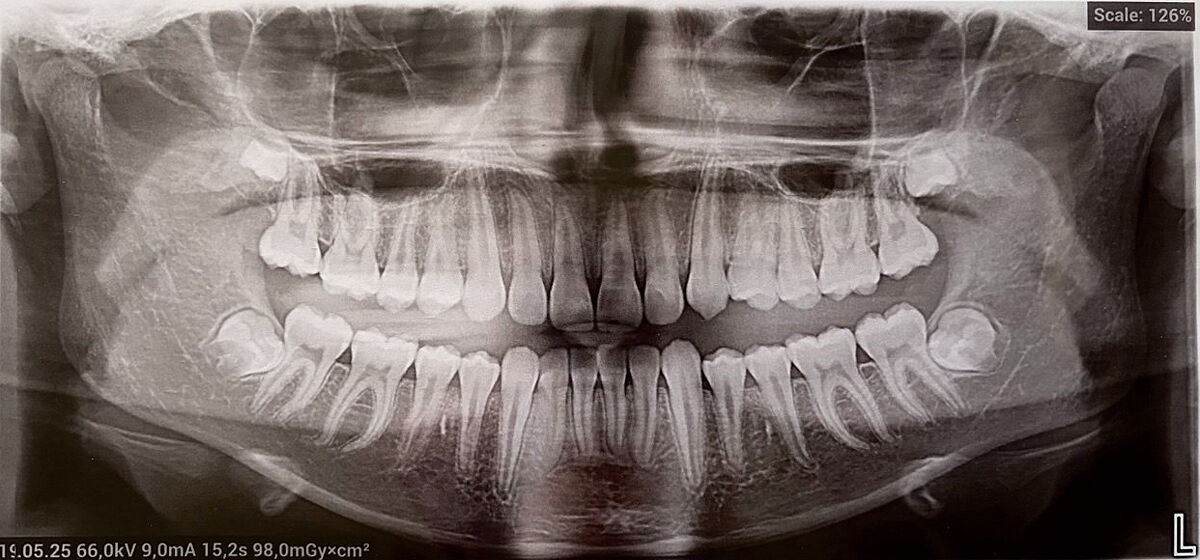

Сину 13 років. Тиждень тому почав скаржитись на ниючу біль в районі зубу мудрості. Зробили знімок, проконсультувалися з стоматологом.

Але додав, якщо за тиждень-два не пройде біль, або стане сильніше, то треба видаляти, бо зуб так лежить (на фото нижня ліва сторона... правий теж так лежить, але не турбує)

На снимках почти нет корней у них. Это из за возраста? По теме. Удаляйте. Моя тетя удалила дочке вроде в 14. Все 4 сразу под седацией. Считаю она молодец. Та неделю промучилась и забыла навсегда про эту проблему. Эти зубы позже могут испортить весь зубной нижний ряд.

так, ще не до кінця сформовані...

На фото теж зародки? Бо не бачу коренів. Їх легше видаляти як ви вважаєте?

у нас так само.рвати поки нема коріння. ми видаляли зародки.коли підуть коріння = буде важче і довше,глибші рани. зараз це на 3 дні припухлості і все.припухлість дасть нижній зуб.

Наш стоматолог теж каже, що зародки легше видалити, ніж коли вже корень є